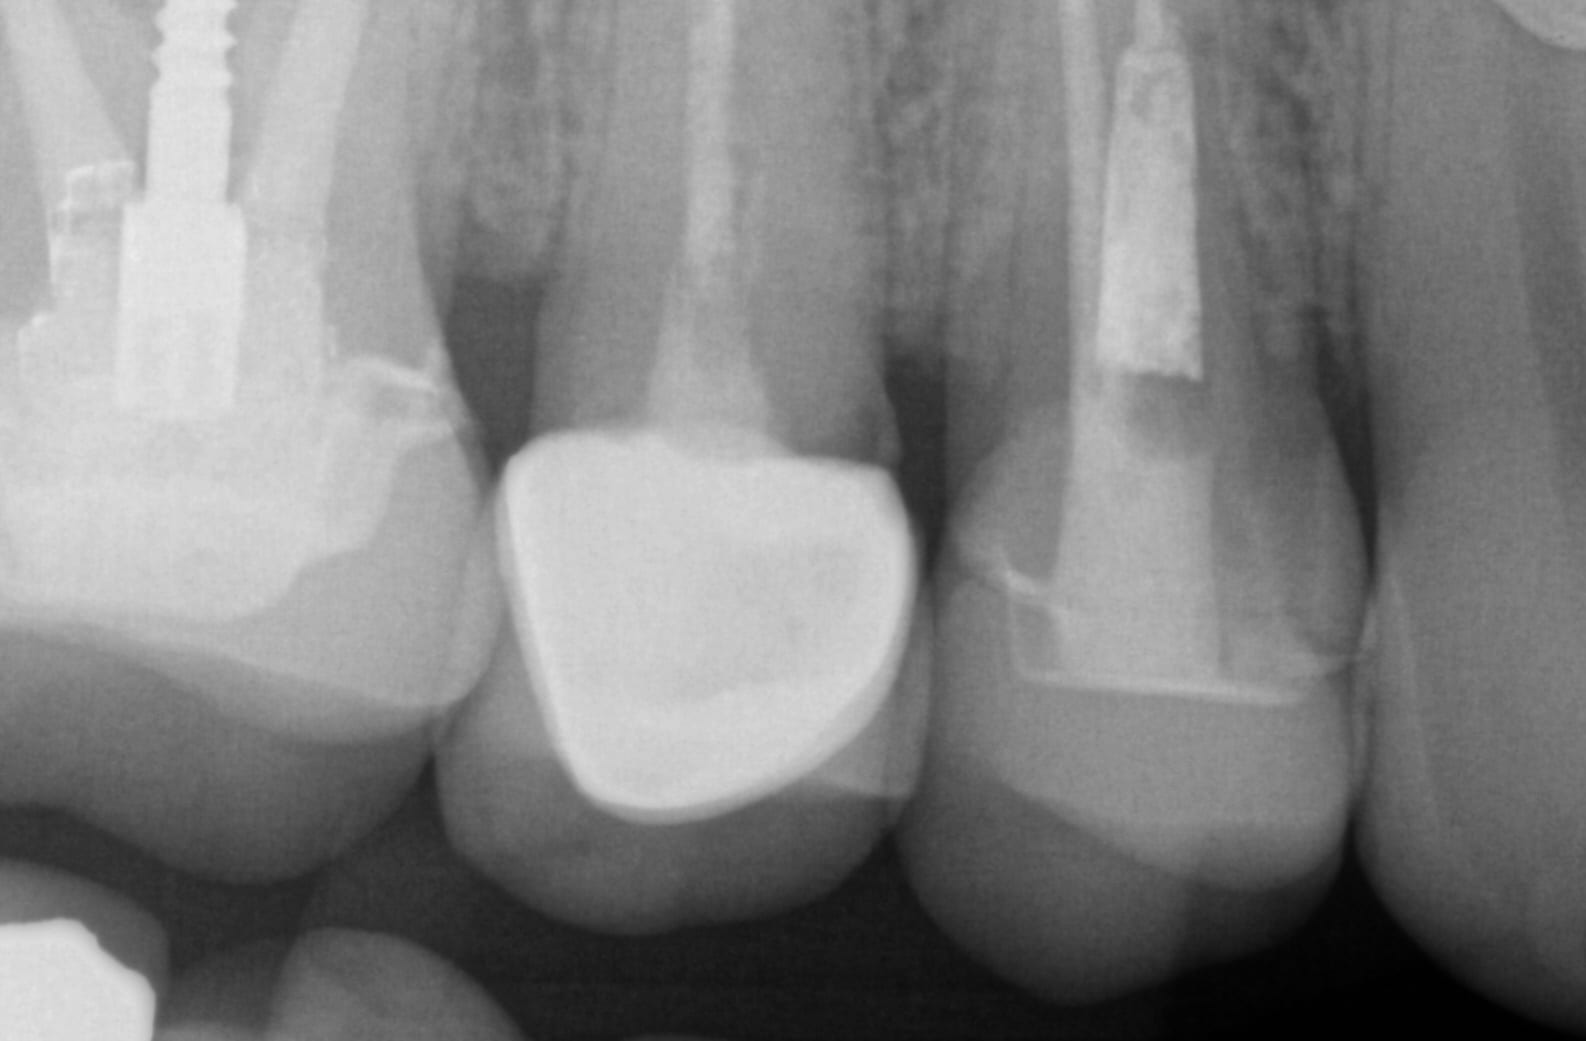

In this clinical presentation, we demonstrate the removal of a crown that has recurrent decay. The bleeding tissue was managed with a double cord technique and expasyl and the margin was captured with the medit i500. The margin was also defined in the native imaging software which allows the user to visualize the detail before designing it or send it off to the lab. Once the case is transferred to cad software, the designed margins carry through and there is an opportunity to modify it